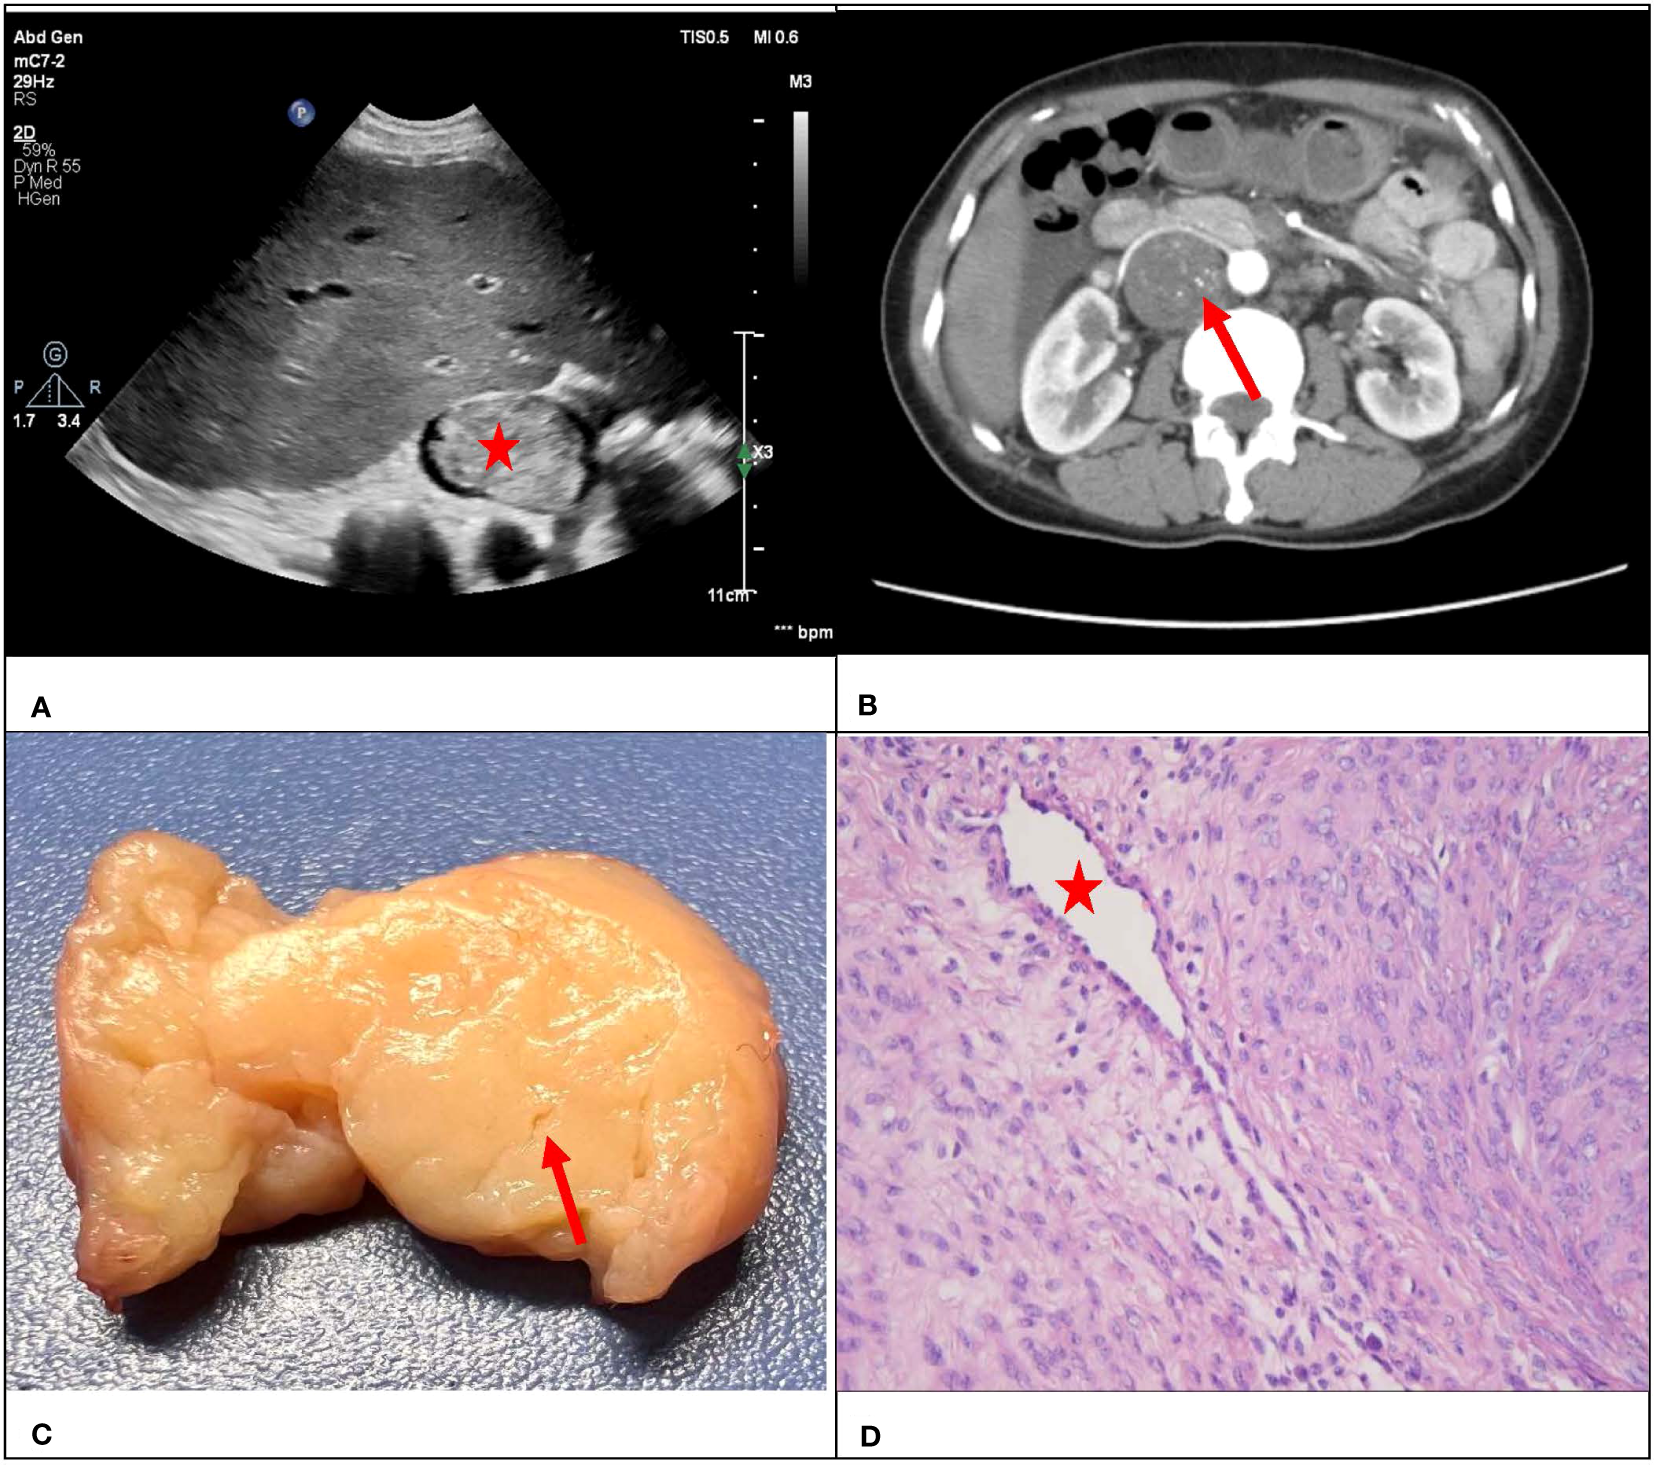

Consistency was observed between the ultrasound presentations and the pathological features in the 67 IVLs. The transverse section of the 20 tubular lesions exhibited a hollow tubular structure with a cystic appearance (Figure 4), whereas the solid cast lesions displayed a tiny lumen-like structure (Figure 5). Histopathologically, all lesions demonstrated spindle cells arranged in bundles, reduced karyokinesis, and the presence of lumens of small blood vessels.

Figure 5

A 47-year-old female with a surgical pathology result of IVL. Figure (A) showed a conventional ultrasound grayscale image, with no “sieve hole sign” on the transverse section (red star). Transverse section of enhanced CT in figure (B) showed uneven enhancement of the lesion, presenting a small tiny “sieve hole sign”(red arrow). Figure (C) showed a fissure like appearance in the transverse section of the lesion (red arrow), while figure (D) showed the internal cavity structure of the lesion under a microscope (red star).